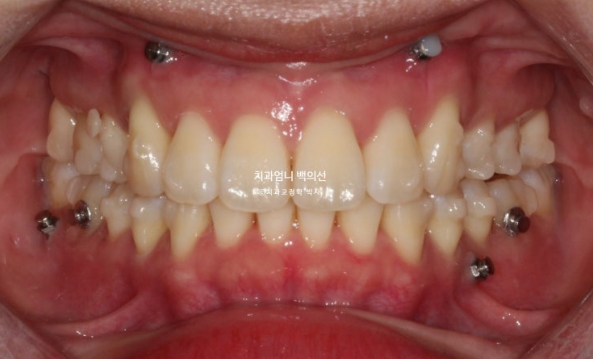

25.01

개선된 과개교합과 일치된 중심선

앞니 뻗침도 많이 좋아졌습니다.

23.02-25.01

전 후 비교입니다.

총 치료기간은 1년 11개월이고 실제 장치를 낀 기간은 1년 9개월입니다.